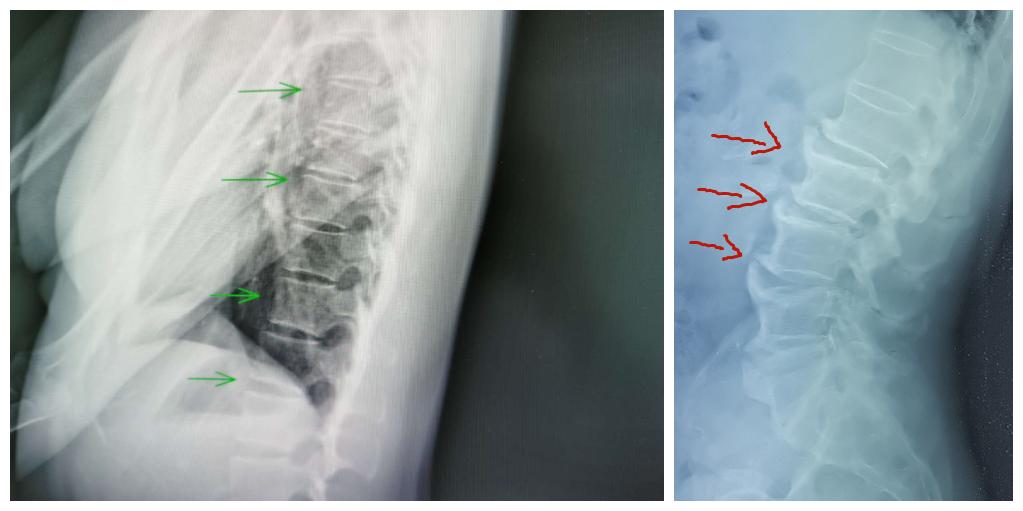

弥漫性特发性骨质增生症多见于老年人,是影像学检查发现的一种以脊椎及脊椎韧带,特别是胸椎前缘及外侧韧带广泛骨化为主要特征的骨关节退变性病变。X线表现具有特异性,影像学表现至少有连续4个椎体的前外侧缘钙化或骨化,在椎间隙水平骨化带增厚隆起而使其成为波浪状,骨化带与椎体间可见一条透明带。

左图正常骨质,右图骨质增生